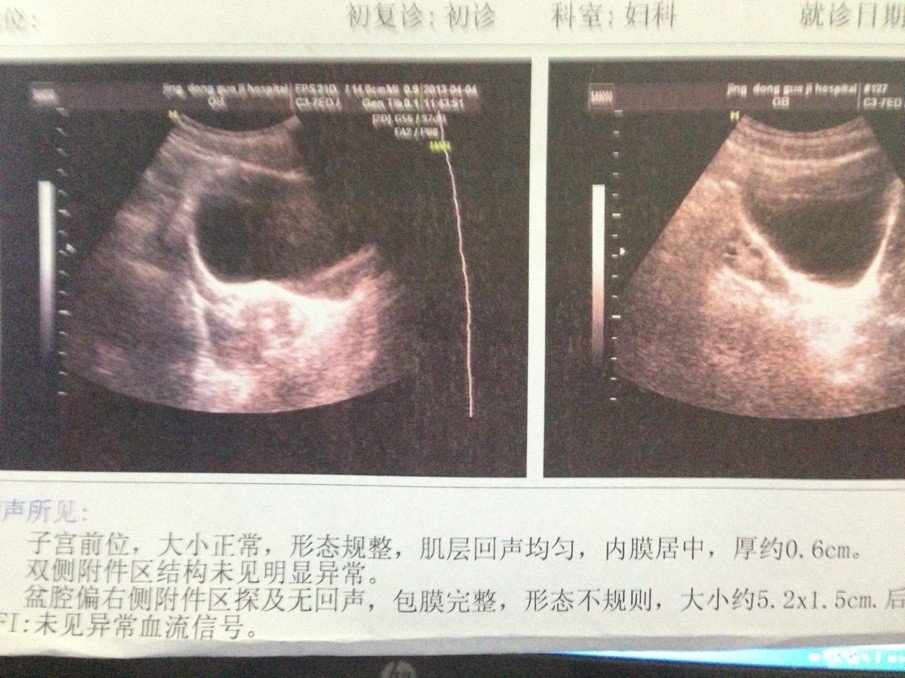

帮忙看看我女友的B超单子,2个月没来月经了,没有怀孕,看看是不是卵巢囊肿,该怎么治疗?谢谢大家了

按这张揭乡单子来截毫说,是还不会来月经的,建议查一个性激素香耀基六项,看看激素水平,至于右侧附件囊肿,可以先观察看看

按照以上超声检查结果,考虑卵巢囊肿,良性可能,尺寸较大,建议手术切除。

B超都说了性质待定,现在只能说最可能是什么。 可能性一:卵巢囊肿 可能性二:巧克力囊肿 可能性三:其他